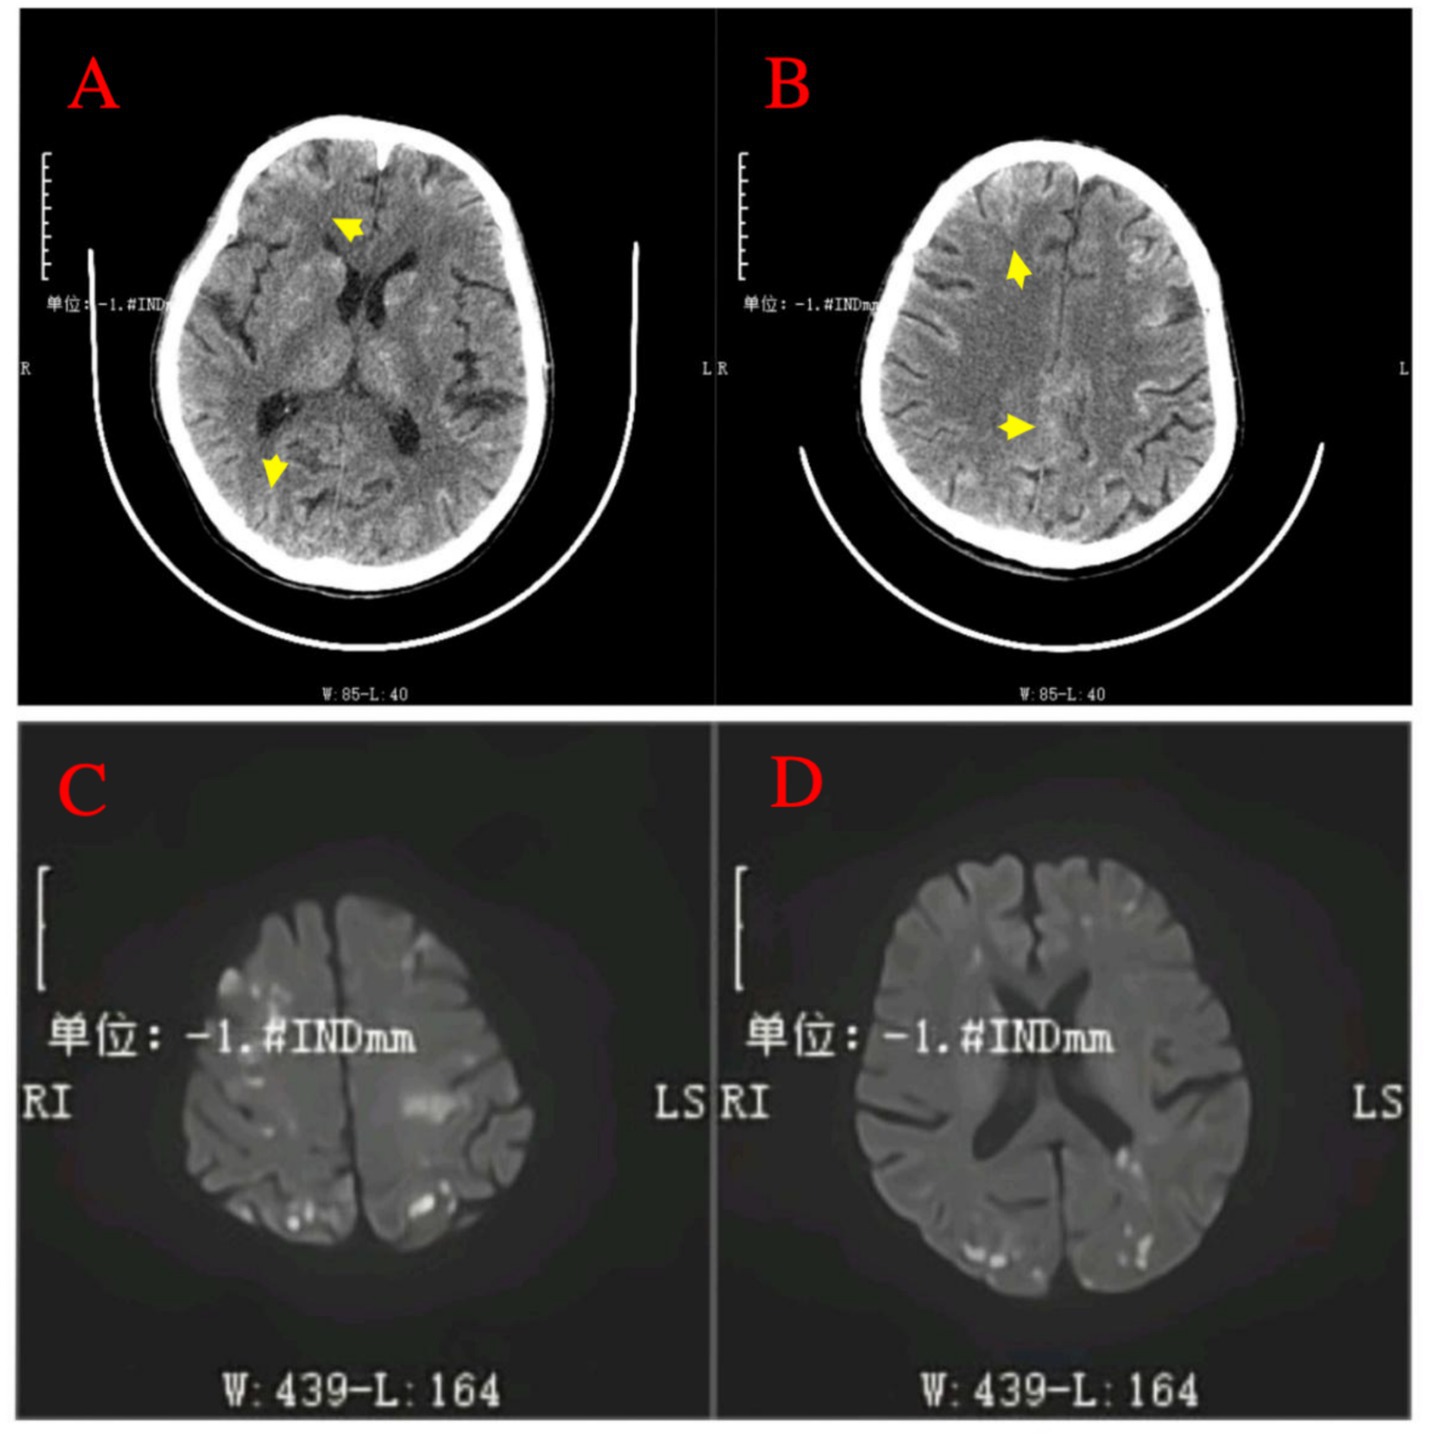

A 64-year-old male patient with multiple HCCs and portal vein invasion (Figure 1A) was classified as Child–Pugh B. Preoperative tumor markers showed an alpha-fetoprotein (AFP) level of 12,263.96 ng/mL (reference range: <10.0 ng/mL) and carcinoembryonic antigen (CEA) of 16.4 ng/mL (reference range: <10.0 ng/mL). Laboratory tests revealed a white blood cell count of 9.43 × 109/L (reference range: 4.0–10.0 × 109/L) and platelet count of 195 × 109/L (reference range: 100–300 × 109/L). Liver function tests showed albumin 32.7 g/L (reference range: 40–55 g/L), aspartate aminotransferase (AST) 843.6 U/L (reference range: 15–40 U/L), alanine aminotransferase (ALT) 238.8 U/L (reference range: 9–50 U/L), total bilirubin (TBIL) 34.8 μmol/L (reference range: 0–26 μmol/L), direct bilirubin (DBIL) 14.90 μmol/L (reference range: 0–6.8 μmol/L), and indirect bilirubin (IBIL) 19.9 μmol/L (reference range: 0–17.0 μmol/L). Renal function was normal. Transthoracic echocardiography revealed no atrial septal defect or other intracardiac shunts. The patient underwent the first TACE. Given the tumor’s diameter exceeding 130 mm, the procedure was performed under close monitoring to ensure no reflux of lipiodol. A total of 40 mL of lipiodol, 2 mg of raltitrexed, and 20 mg of lobaplatin were infused. Due to the patient’s family’s limited financial resources and refusal to use coil embolization, gelatin sponge particles (560–710 μm) were used to block the vessels. Following embolization, hepatic arteriography was repeated, confirming the successful closure of the arteriovenous fistula, after which the tumor was embolized with lipiodol. Intraoperative angiography demonstrated an arterioportal shunt (Figure 1B). Twenty hours postoperatively, the patient developed decreased consciousness and right-sided weakness with numbness, without headache or visual disturbances. Physical examination revealed blood pressure of 116/75 mmHg (1 mmHg = 0.133 kPa), with normal pulse, respiratory rate, and body temperature. Neurological examination showed a clear mental status with appropriate responses, right nasolabial fold flattening, midline tongue protrusion, right upper limb muscle strength grade 2, other limbs grade 5, decreased superficial sensation on the right side, and positive Babinski sign on the right; no other pathological signs were noted. Head CT performed 20 h and 30 min postoperatively revealed multiple abnormal density lesions in the bilateral cerebral cortex, subcortical regions, basal ganglia, thalami, and periventricular areas (Figures 2A,B). MRI performed 24 h postoperatively, including diffusion-weighted imaging (DWI), showed scattered punctate and patchy hyperintense or slightly hyperintense lesions in the bilateral frontal, temporal, parietal, and occipital lobes as well as the basal ganglia, with poorly defined margins (Figures 2C,D). Neurology consultation suggested cerebral embolism secondary to iodized oil. The patient’s consciousness gradually improved over the following week; however, right-sided weakness persisted without significant recovery. The patient remains under follow-up.

Figure 2

Post-procedural neuroimaging findings of cerebral lipiodol embolism. (A,B) Non-contrast head CT scans post-TACE reveal multiple hyperdense foci (indicative of radiopaque Lipiodol deposition) distributed across bilateral cerebral cortices, subcortical regions, basal ganglia, thalamus, and periventricular areas (arrows). (C,D) Diffusion-weighted imaging (DWI) MRI sequence performed 24 h after TACE confirms numerous scattered punctate and patchy areas of high signal intensity within the bilateral frontal, temporal, parietal, occipital lobes, and basal ganglia.